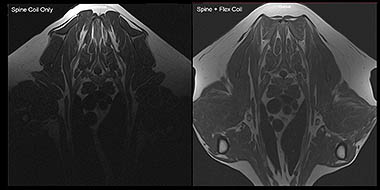

After the recent launch of the innovative PetVet MRI, Hallmarq Veterinary Imaging has continued on its pioneering path to develop the first dual coil veterinary specific MRI. The ground-breaking feat of engineering incorporates the ability to use two RF receive coils simultaneously to give vets greater scope to investigate challenging anatomical regions and obtain superior images.

Just as two heads are said to be better than one, Hallmarq has demonstrated that combining two radiofrequency (RF) coils – the components responsible for receiving the electromagnetic waves - provides a significant boost in signal sensitivity across larger body areas. This is particularly advantageous for imaging bigger breeds of dog and for scanning difficult areas such as the brachial plexus region.

Dr Steve Roberts, Director of Hallmarq Veterinary Imaging, explains how the coils work in combination to gives vets a clearer picture, “Placing a second flex coil on the chest of the animal in addition to the spine coil overcomes the natural decrease in sensitivity that occurs with increasing chest depth. The patient is essentially ‘sandwiched’ between the two coils, resulting in great magnetic resonance images - even in those challenging larger breeds and for areas that are traditionally tricky to image well.”

Eduardo Fraga Manteiga, radiologist at Southern Countries Veterinary Specialists, who has had been using the Hallmarq system for the past year, said, ‘The spine and flex dual coil system offers significantly improved performance when compared to its single coil counterpart. This case was the first clinical demonstration of the ability to use the multiple coil system in a veterinary MRI machine and showed promising results for future application.‘